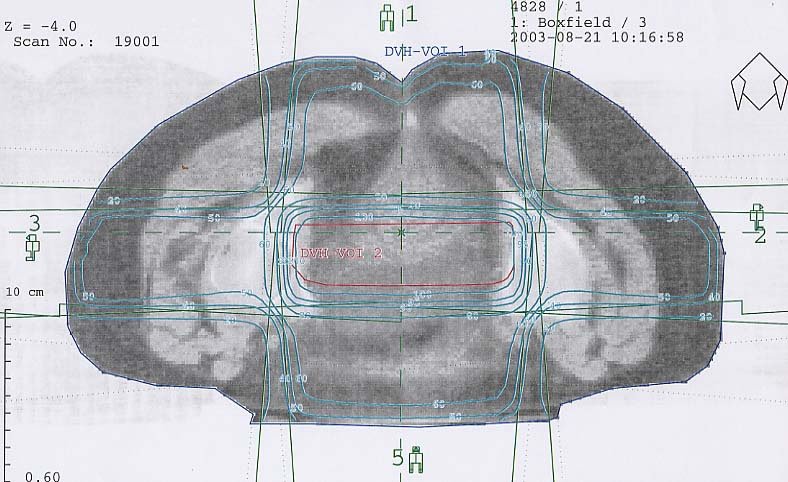

Gynäkologische Tumore des Beckens: Bestrahlungsplan